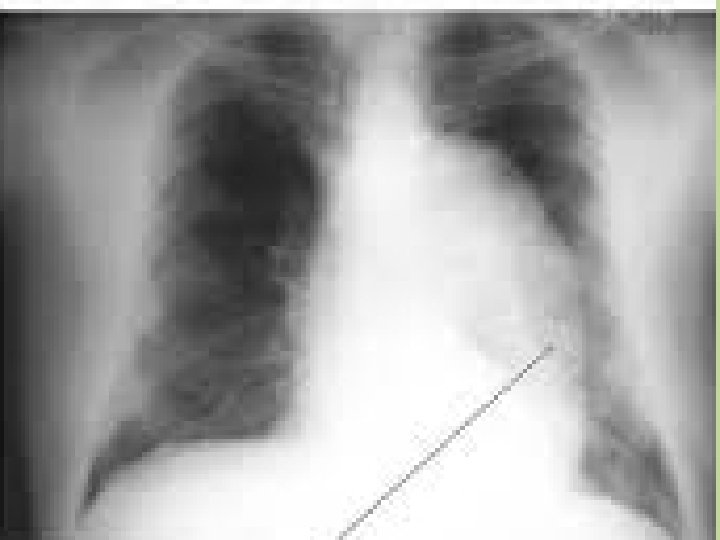

Dor Torácica ventilatório dependente Não catastróficas • Pneumonia: Febre, tosse cheia; expectoração; crepitações e infiltrado pulmonar • Colher culturas e iniciar antibiotico precoce